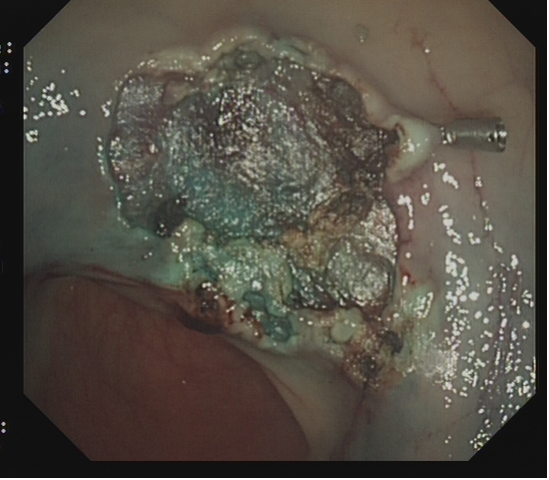

对于大型Ⅰp病变,除以上注意事项外,应采用热圈套方式切除,切除前应于蒂根部充分黏膜下注射(经内镜注射针将2~10 mLl万单位的肾上腺素+亚甲蓝+生理盐水混合液注射于黏膜下,边退针边注射),致使蒂部充分隆起,易于切除(图 3),切除过程中病变应避免接触肠壁,以免形成闭合回路,灼伤肠壁。

需要注意的是大型Ⅰp型息肉若蒂部较粗,则可能含粗大滋养血管,切除后极易出血。切除过程中可采用凝-切-凝的方式,减少出血风险。部分较大息肉,可采取分块切除方式,降低操作难度,但此法不利于病理评估。